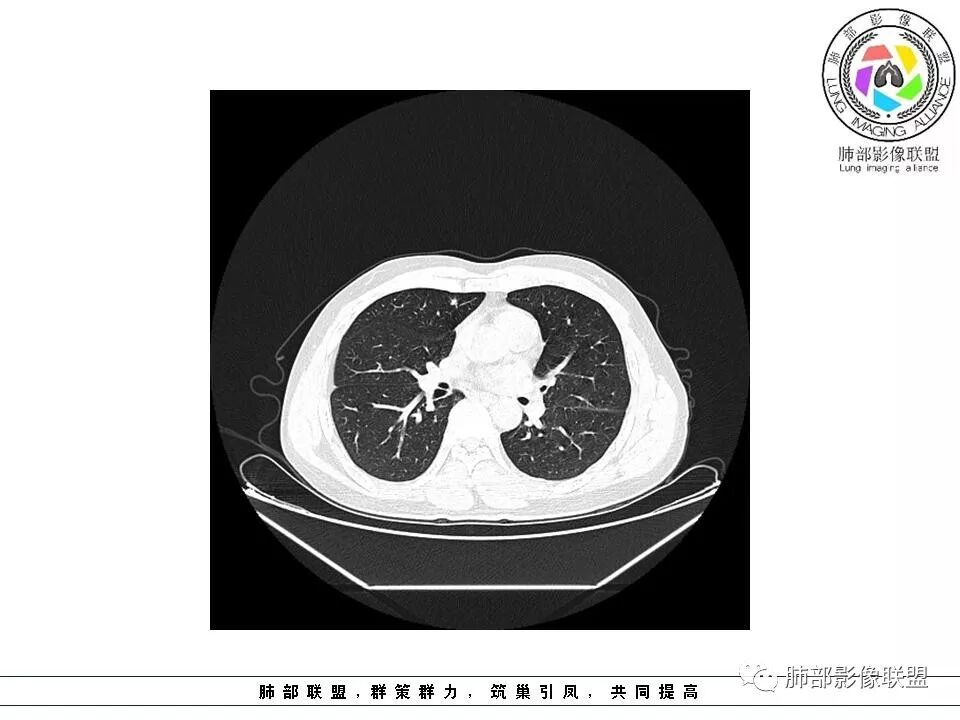

南边:51岁男性,体检发现右肺结节这个年龄段的男性,啥都可以发生,也属于肺癌的高危人群南边:首先是实性还是GGO?好像实性吧

如果实性病变,边缘收缩,可以考虑炎性, 但是边缘有边界清楚GGO,一定要警惕恶性,还有粗短毛刺更要小心撇开其它,看到这个图,除非你怀疑假象,不然就是要考虑腺癌的可能

边界清楚GGO,短毛刺,这要小心瘢痕癌可以多为腺癌复查没变化,与血供有关,属于休眠期张国祯教授的理论:腺瘤样增生、原位癌都属于偏良性,就是没有侵袭性;以后发展——侵袭可以,不变可以,部分可能还会凋亡(比较少)

原位腺癌